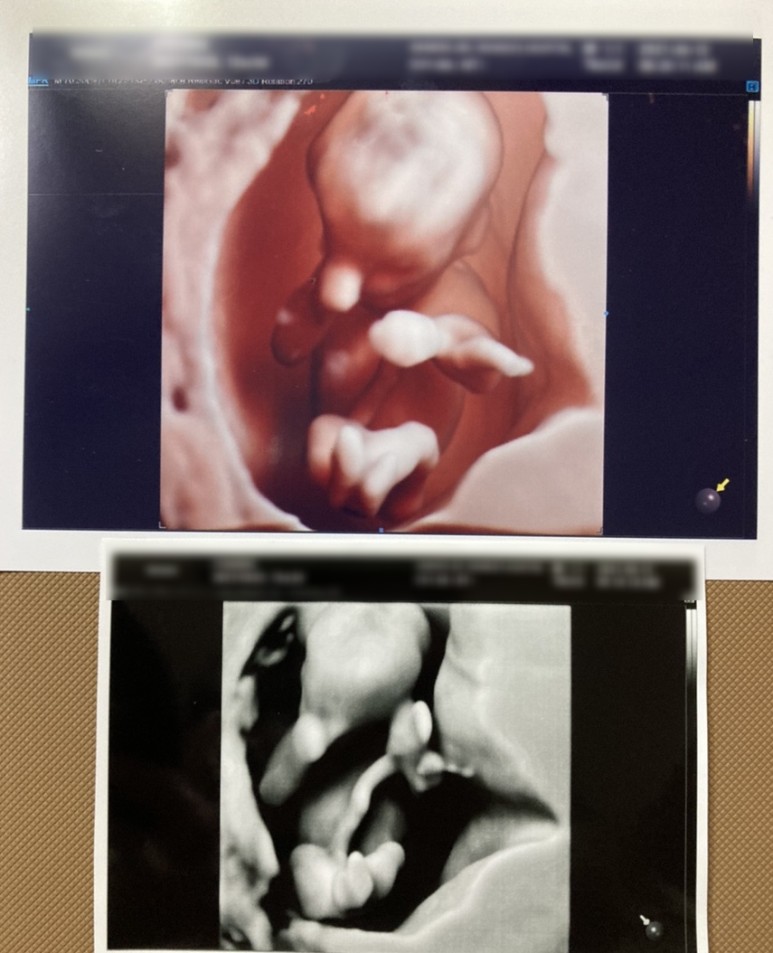

이제 제법 사람 같네.8주 동안 매주 병원에 다녀왔다.그냥 한방이 건강한지 보고 싶어서 ㅎㅎ 또.. 병원 검진휴가 하루 쉬면서 남편이랑 데이트도 좋아하고..

왼쪽사진은 한방을 밑에서 찍은모습이고 궁에들어와 양다리www11주차가 된 한방은 이미 꽤 사람같았다. 그리고 이날 초음파를 봤는데, 아무리 움직여도, 아기 집을 팡팡 발로 차고, 손도 엉망진창이여서, 너무 귀여웠다. 벌써부터 도치맘…?